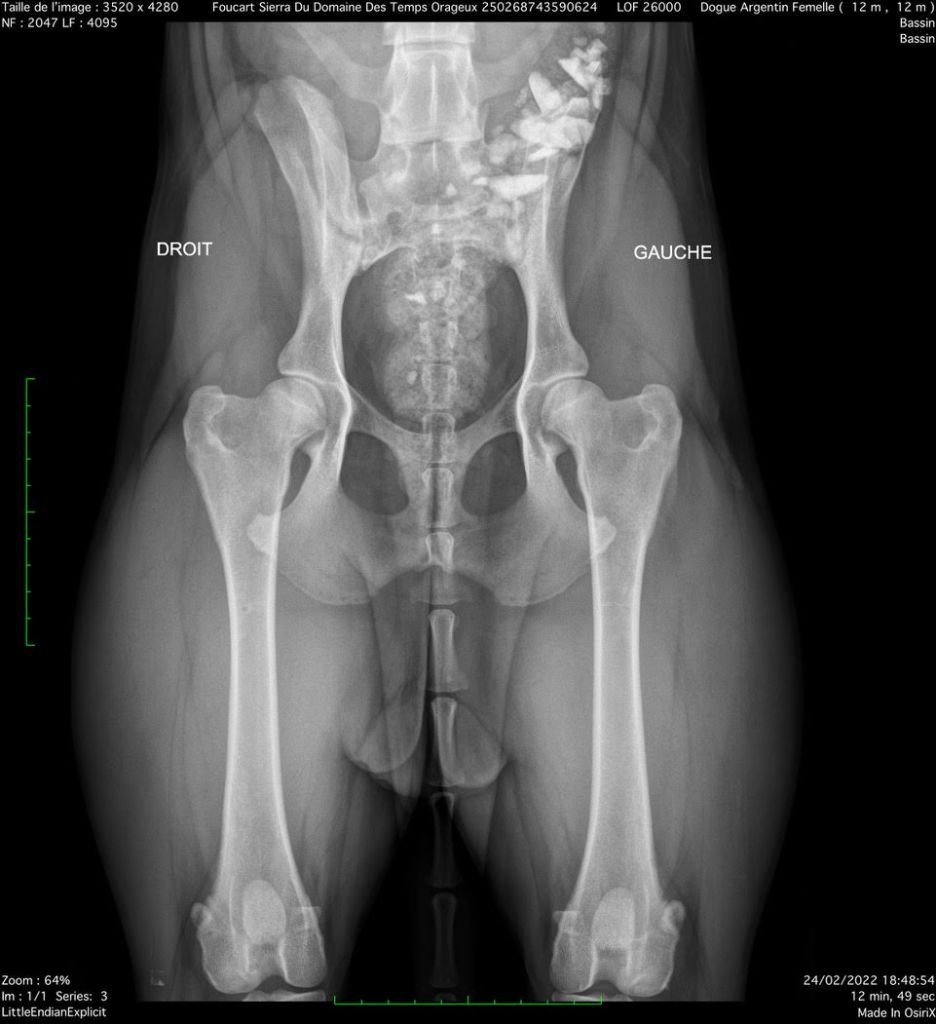

- Radios des hanches : A/A OFFICIEL (FR)